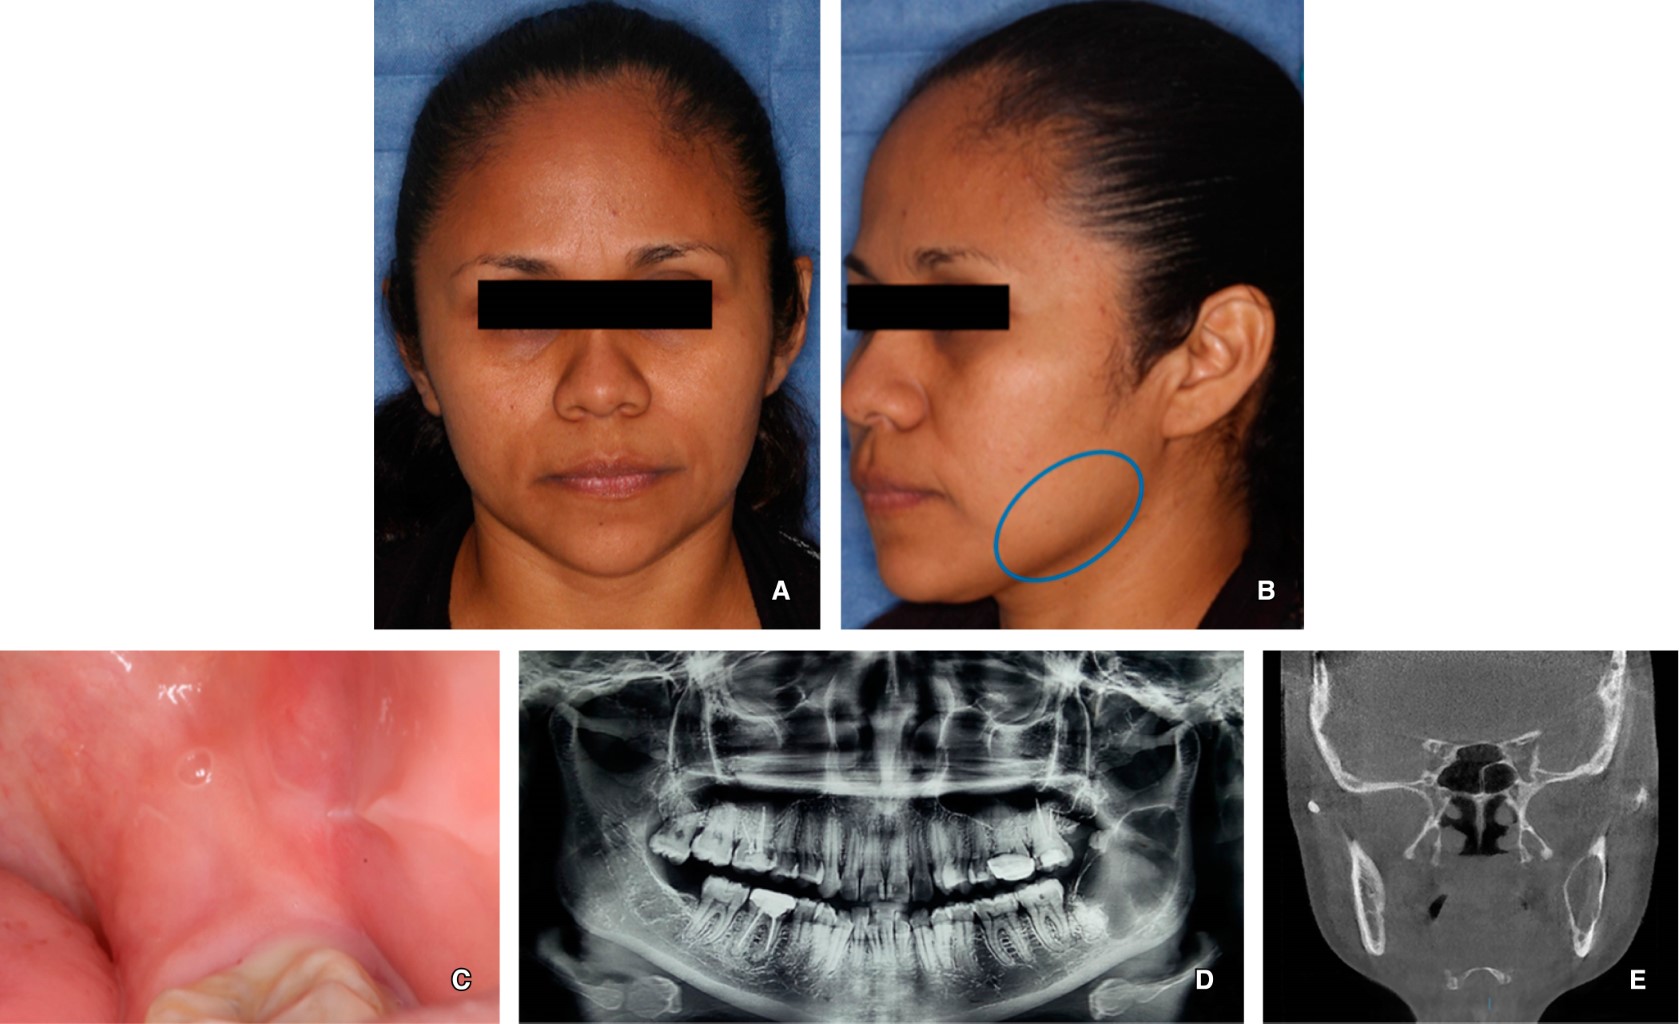

. Journey of okc from cyst to tumor to cyst again. Implant surgery for the placement of dental implants is performed after full bony consolidation of the bone grafts to complete full oral rehabilitation for the patient. Biopsy results came back positive with the diagnosis of odontogenic keratocyst in the left mandibular region.

The most appropriate surgical approaches for the successful. Nancy Herbst walks through how to properly remove an Odontogenic KeratocystLike and subscribe for moreUnion City Oral Surgery Group is located in Union. Case Report Figure 4.

Dental professionals will typically recommend a test like an MRI CT or X-ray. Odontogenic keratocyst are surgically removed by marsupialisation enucleation and chemical curettage with carnoys solution. In rare instances particularly large cysts may require resection and bone grafting.

CT scans in axial and coronal planes. Long-term follow-up with monitoring by X-ray is important as if these cysts are left untreated they can become quite large and locally destructive. We recommend the following protocol in the management of large mandibular OKC.

Cyst can be removed by open as well as endoscopic approach. Imaging studies and a biopsy were obtained at the hospital. Large odontogenic keratocysts sometimes are treated initially by cystotomy and insertion of a drainage tube which can promote shrinkage of the lesion and fibrous thickening of the cyst wall before subsequent total removal.